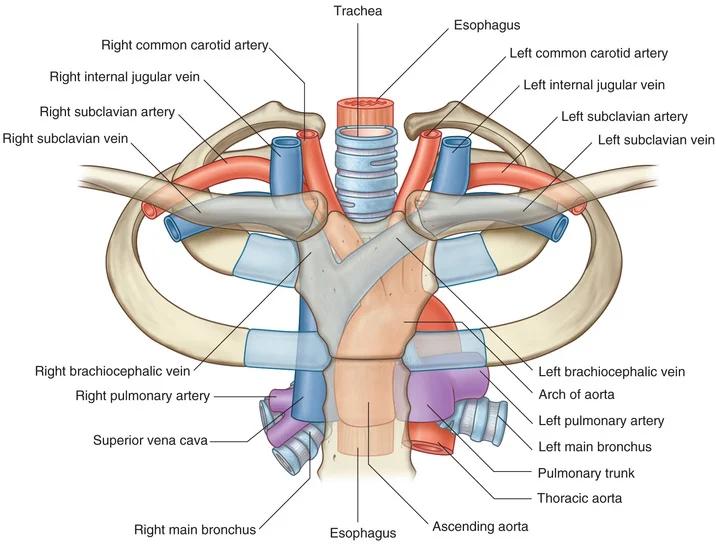

Fig 3.04: Arcus aortae

omslagplooi pericardium trachea esophagus tr. pulmonalis lig. arteriosum isthmus aortae (vernauwing lumen t.h.v. lig. arteriosum) linker n vagus (X) -

zijtakken arcus aorta

tr. brachiocephalicus

a subclavia dextra a carotis communis dextra

a carotis communis sinistra a subclavia sinistra (a thyroidea ima)

Fig 3.05: tr. brachiocephalicus

sternum clavicula rib I trachea (cyaan) tuberculum m. scalenus anterior m scalenus anterior plexus brachialis -

zijtakken tr. brachiocephalicus

a carotis communis dextra a subclavia dextra (uit achterste scalenuspoort)

v subclavia dextra (uit voorste scalenuspoort) a carotis communis sinistra (herhaling) a subclavia sinistra (herhaling) linker n vagus + n recurrens (herhaling) -